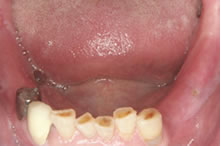

- 【術前】

- 左右の奥歯が無い状態です。

噛みあわせが強いため前歯が磨り減っています。